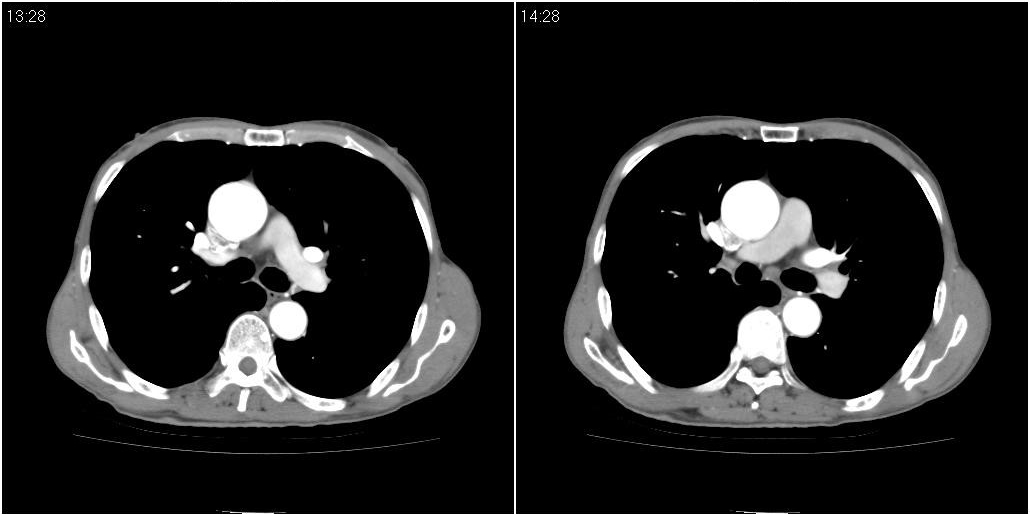

标题: CT25416:男性,70岁。胸片发现右下肺斑片状阴影

以下是ct检查的情况:

标题: ct增强: